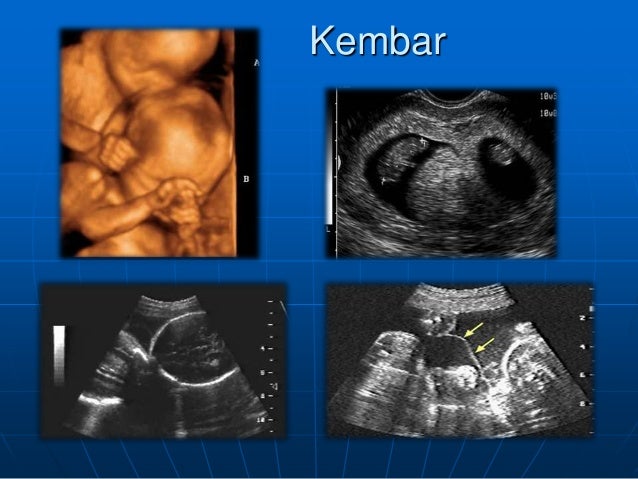

USG KEHAMILAN 6 MINGGU “suara jantungnya bikin takjub” - YouTube Story of My Journey: USG Kehamilan 6 Minggu Begini Kondisi Janin di Usia Kehamilan 1 sampai 6 Minggu Kehamilan - Tribun Sumsel Kehamilan Pertama - USG 6 Minggu (1 Bulan di Diagnosa Hamil Kosong) - YouTube Kehamilan Pertama - USG 6 Minggu (1 Bulan di Diagnosa Hamil Kosong) - YouTube usg 6 minggu Memasuki 6 minggu kehamilan – Acuriousity Usg hamil 6 week 4 day (menurut usg) 6week 5day (menurut hph Gambaran Hasil Usg Kehamilan 5 Minggu Yang Perlu Diperhatikan - Hamil.co.id USG KEHAMILAN FULL 6 MINGGU - SUDAH TERLIHAT KANTONG DAN JANIN! FETAL DEVELOPMENT 6 WEEKS - YouTube USG Pertama Kehamilan 6 Minggu | KISAH KASIH BUNDA Ini Dia Cara Membaca Hasil USG dengan mudah - Mamapapa.id % 5 Langkah Membaca Hasil USG yang Bisa Bunda Pelajari Cara Membaca Hasil USG yang Benar, Wajib Tahu! Gambaran Hasil Usg Kehamilan 6 Minggu Yang Normal - Hamil.co.id JANIN BELUM TERLIHAT SAAT USG? JANGAN KHAWATIR, MOMS! - susistory Diary Kehamilan: Cerita Kehamilan Pertama, Pertama Tahu Hamil – ranselriri Mengenal Kehamilan Kosong atau Blighted Ovum (BO) - Bidanku.com Ciri Kehamilan 6 Minggu Yang Sehat, Harap Hati-hati Mandi Air Hangat! Ukuran Kantong Janin 6 Minggu Yang Normal Dan Tidak Bermasalah - Hamil.co.id Hamil Kosong Atau Blighted Ovum (BO) – . Hasil USG hamil 6 Minggu sudah terlihat embrio nya’ tp keadaan nya lemah. - YouTube Periksa Kehamilan – ayyunie’s Blog Kenali Cara Membaca Hasil USG Untuk Tahu Kondisi Bayi - Ibupedia USG 2D dan 4D - USG KEHAMILAN KEMBAR TIGA USIA KEHAMILAN 6… Cara Membaca Hasil USG, Simak Ini Panduannya USG dasar dalam kehamilan Tes Ini Pastikan Kehamilan Kembar | Republika Online Mengetahui Tanda-Tanda Kehamilan Kosong - Bidanku.com USG usia kehamilan 6 minggu 2 hari - YouTube 10 Tanda Tanda Hamil Kosong - Penyebab, Perawatan dan Pencegahan - Hamil .co.id USG [1] : Enam Minggu Lima Hari – Jejak-jejak yang Terserak Pengalaman saat Alami Kehamilan Kosong (Blighted Ovum) Halaman all - Kompasiana.com LDM, Karier dan Trimester Pertama Kehamilan Manfaat USG untuk Ibu Hamil dan Janin - Ibupedia BILIK SONOGRAFER : Kehamilan Awal (Kehamilan Trimester 1) Hamil 6 Minggu dengan 2 Kantong kehamilan - IbuHamil.com Kapan Denyut Jantung Janin Bisa Terdeteksi? | HonestDocs Bagaimana Cara Membaca Hasil USG? • Hello Sehat USG kehamilan (6minggu) - YouTube hasil usg 6w1d - IbuHamil.com Blighted Ovum bukan ya ? | Olinehai’s Blog Hamil Setelah Keguguran - Mommies Daily Manjakani Kanza Asli Aceh: Hasil Usg Usia Kehamilan 6 Bulan USG dasar dalam kehamilan Usia hamil 6 minggu, sudah ada detak jantung guys - YouTube Syahnaz Sadiqah Hamil 8 Minggu, Hasil USG Tunjukkan Dua Janin Sekaligus - Tribun Pontianak Mengandung bayi kembar, satu janin menghilang, vanishing twin syndrome | theAsianparent Indonesia Ibu Hamil, Ini 12 Tandanya Bayi di Dalam Kandunganmu Sehat | BukaReview 6 Fakta Hamil Kosong atau Blighted Ovum. Gejalanya Hamil, tapi Janin Tak Berkembang Sempurna Bumil Wajib Tahu, Inilah Penyebab Bayi Sungsang dan Cara Mengatasinya Berapa Kali USG Saat Hamil Harus Dilakukan? USG dasar dalam kehamilan Perkembangan Kehamilan di Minggu 6 - Tips Bumil Balita 3 Kemungkinan Penyebab Janin Tidak Terlihat di USG spogsemarang Instagram posts (photos and videos) - Picuki.com Mengetahui Usia Kehamilan Dengan USG – . Catatan Calon Ayah # 6: USG Kehamilan | WebLog Andika Priyandana Ini Dia Cara Membaca Hasil USG dengan mudah - Mamapapa.id % Evan Reisha - Kontrol Kandungan Ke-6 (Trimester 2-3, 27W6D) USG Dede bayii 6 minggu || Hamil anak kdua ll - YouTube Pengalaman Hamil Kembar - The Urban Mama bunda apakah ada yang seperti sy usia kehamilan 6-7 min Mulai Rasakan Mual, Ini 6 Momen Zaskia Sungkar Cek USG Janin Pertama Kali - Hot Liputan6.com USG dasar dalam kehamilan Story of My Journey: USG Kehamilan 19 Minggu Kapan Ibu Hamil Sebaiknya Melakukan USG? Mengenal Kehamilan Kosong atau Blighted Ovum (BO) - Kompasiana.com Selamat Datang Anak Kembar Yang Manis – TUKANG CERITA! Kehamilan Pertama - USG 6 Minggu (1 Bulan di Diagnosa Hamil Kosong) - YouTube My Very first “first trimester” – Let The World Surprise You ukuran janin 5 minggu itu brp cm sih bun? - IbuHamil.com Pregnancy | travelvita | Halaman 3 Perkembangan Janin Usia 6 Minggu - Bidanku.com Diagnosis Kehamilan Ektopik - Alomedika Dokter Spesialis Kebidanan Dan Penyakit Kandungan Usia Kandungan 6 Minggu Mulai Rawan Hamil Anggur » Bogor Today Perkembangan Kehamilan 6 Minggu - Mamapapa.id % Mulai Rasakan Mual, Ini 6 Momen Zaskia Sungkar Cek USG Janin Pertama Kali - Hot Liputan6.com USG dasar dalam kehamilan Kapan Ibu Hamil Mulai Merasakan Gerakan Janin? - kumparan.com Usia Kehamilan 6 Minggu Belum Terlihat Janin - Info Seputar Kehamilan CeRiTa cHa: Para Ibu Hamil, Ini Keluhan yang Biasanya Muncul Saat Tri Semester Pertama Kehamilan Take and Share — Kami Menunggumu Nak Rekomendasi USG dan Dokter SpOG di Solo | by Diana Nurwidiastuti | Medium Kata Dokter Saat USG Janin di Rahim Saya Hanya Satu, Nyatanya Saya Melahirkan Kembar,’ Bagaimana Kasus Seperti Ini Dapat terjadi? - Semua Halaman - Intisari hamil minggu ke 6 - Perawatan Kesehatan Hamil kosong Tanpa Kuret, Ternyata Ini Dampaknya Moms! flek dan kram di usia janin 6 minggu 6 Hal yang Harus Dipersiapkan saat Pertama Kali Melakukan USG | Popmama.com ukuran janin 5 minggu itu brp cm sih bun? - Halaman 3 - IbuHamil.com USG Baru Bisa Dilakukan Saat Usia Kandungan 4 Minggu, Ini Sebabnya Tanda Dan Gejala Kehamilan 6 Minggu Yang Sehat Serta Normal - Hamil.co.id USG dasar dalam kehamilan Kantung Janin Tidak Bulat Menyebabkan Flek? - kumparan.com SYOK! Dokter Kandungan Ini Kaget Lihat Hasil USG Ibu Hamil, Mencengangkan! - Halaman all - Tribun Manado Perkembangan Janin Usia 6 Minggu Memahami Air Ketuban dan Fungsinya - Alodokter USG [6] : 34 Minggu 2 Hari – Jejak-jejak yang Terserak Usg 4 dimensi, Klinik Metro Medika di perumahan Metro Permata I, jl Metro Permata utama blok E2 no 3 karang tengah, Ciledug., Tangerang (2020)